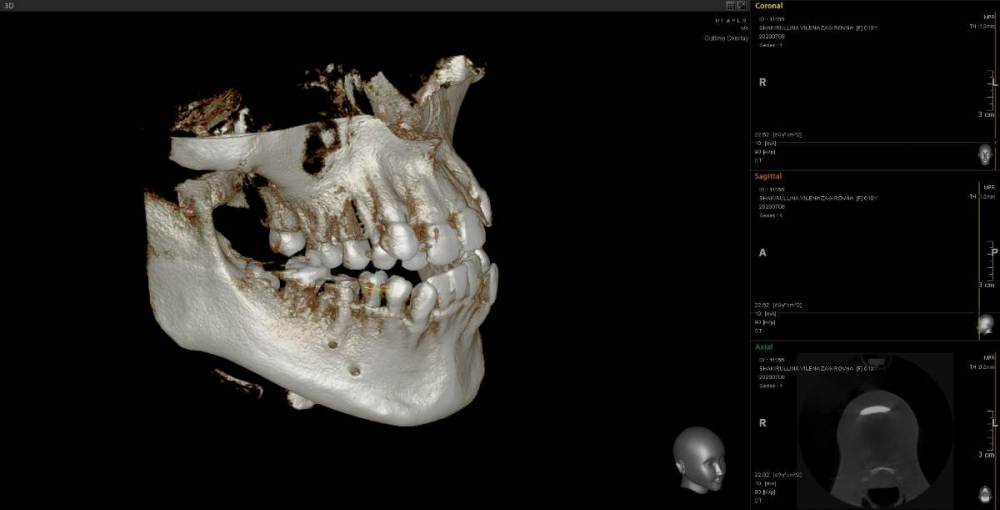

Женька Опубликовано 23 июня, 2021 Поделиться Опубликовано 23 июня, 2021 Коллеги, приветствую. Пришла пациентка с направлением на удаление 1.6-2.6 по ортодонтическим показаниям. Расспросив узнал, что принял решение такое ортодонт, тк премоляры интактны, а вот 1.6 эндодонтически пролечен. 2.6 с пломбой. Вопрос, оправдан ли такой подход? Есть лишь реконструкция КТ. Зубы я конечно не удалил, тк о таком подходе слышу впервые. Связавшись с ортодонтом узнал, что нестандартное удаление... Что думаете? p/s мудрые почему-то пока не удаляем... Ссылка на комментарий

Женька Опубликовано 24 июня, 2021 Автор Поделиться Опубликовано 24 июня, 2021 Поговорил с коллегой-ортодонтом из Перми. Сказала, что случаи удаления 6 это один на миллион?♂️ Ортовинтов в этом случае не будет, сроки лечения без дополнительных опор будут большие, верно? 1 час назад, red_butler сказал: да 1 Ссылка на комментарий

Женька Опубликовано 1 июля, 2021 Автор Поделиться Опубликовано 1 июля, 2021 Коллега мне сказала, что мезиализировать 7 до контакта будет практически нереально, а без доп опор сроки лечения растянутся лет так на 5... Но это норма в нашем захолустье... все ходят по 3-5 лет (я не ортодонт, это может норма, я не знаю?) Ссылка на комментарий